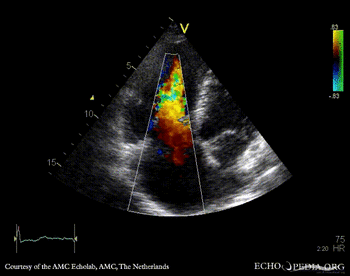

E00348.gif E00349.gif

A4CH: stiff, immobile tricuspid valve A4CH: severe tricuspid regurgitation